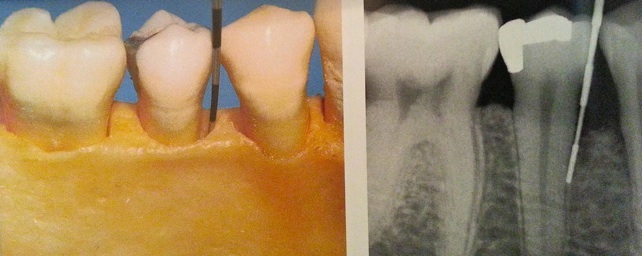

L’atteinte de la furcation interradiculaire est un facteur aggravant.

Résorption osseuse interradiculaire, classification des furcations: